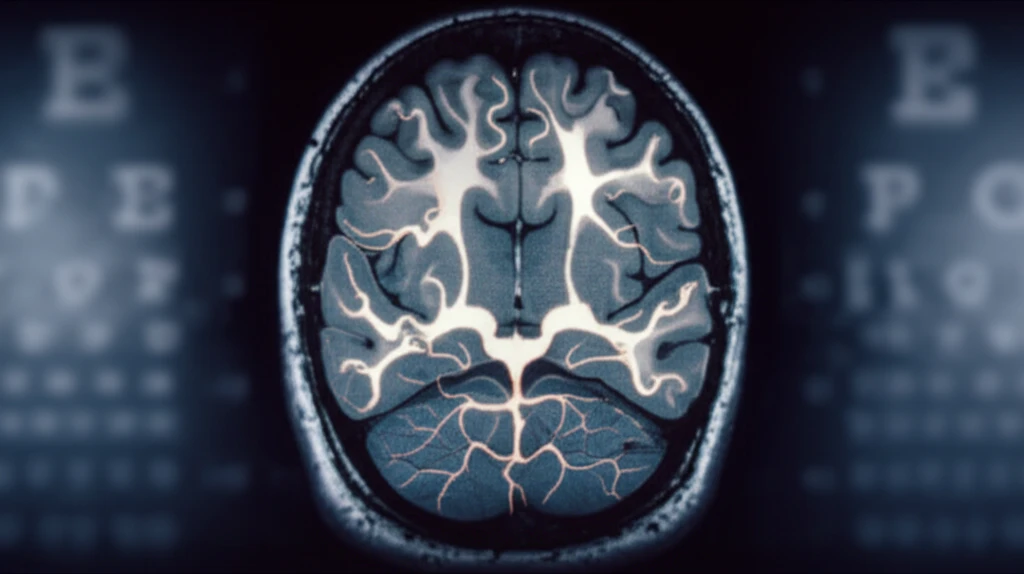

Visual evoked potentials (VEPs) offered an alternative by measuring the brain's response to visual stimuli such as gratings or checkerboards. However, VEPs primarily reflect activity in the primary visual cortex and may not fully capture higher-level visual processing. In cases of psychogenic visual loss or other complex conditions, VEPs might not provide a complete or reliable assessment of a person's functional vision.

Now, groundbreaking research published in Investigative Ophthalmology & Visual Science suggests a promising new approach: using event-related potentials (ERPs), specifically the P300 component, to objectively estimate visual acuity based on optotypes like the Landolt C. This innovative technique goes beyond simple detection and taps into higher-level cognitive processing, potentially offering a more accurate and comprehensive assessment of visual function.

The P300 is a positive-going ERP component that typically peaks between 300 and 600 milliseconds after a stimulus is presented. It’s considered a marker of higher-level cognitive processing, reflecting processes such as attention, working memory, and decision-making. By presenting a series of frequent and infrequent visual stimuli (an oddball paradigm) and recording the brain's electrical activity, researchers can measure the P300 response and gain insights into how the brain processes visual information.